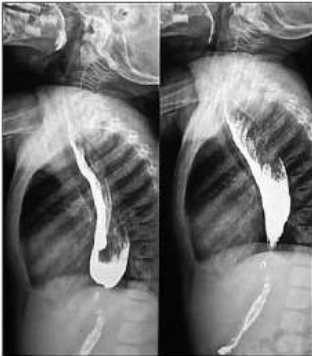

Menina de 8 anos apresenta, há 2 anos, disfagia, regurgitação e perda de peso. Há 6 meses apresenta dor retroesternal e pirose. Após anamnese, exame físico e exames laboratoriais, foi realizado o esôfago-estomago-duodeno (EED) contrastado, com as seguintes imagens:

Enunciado 3028667-1

Analise as afirmativas abaixo sobre a principal hipótese diagnóstica.

I. Esofagite Eosinofílica.

II. Acalasia do cárdia.

III. Doença do refluxo gastroesofágico.

IV. Estenose pilórica.

Estão corretas as afirmativas: